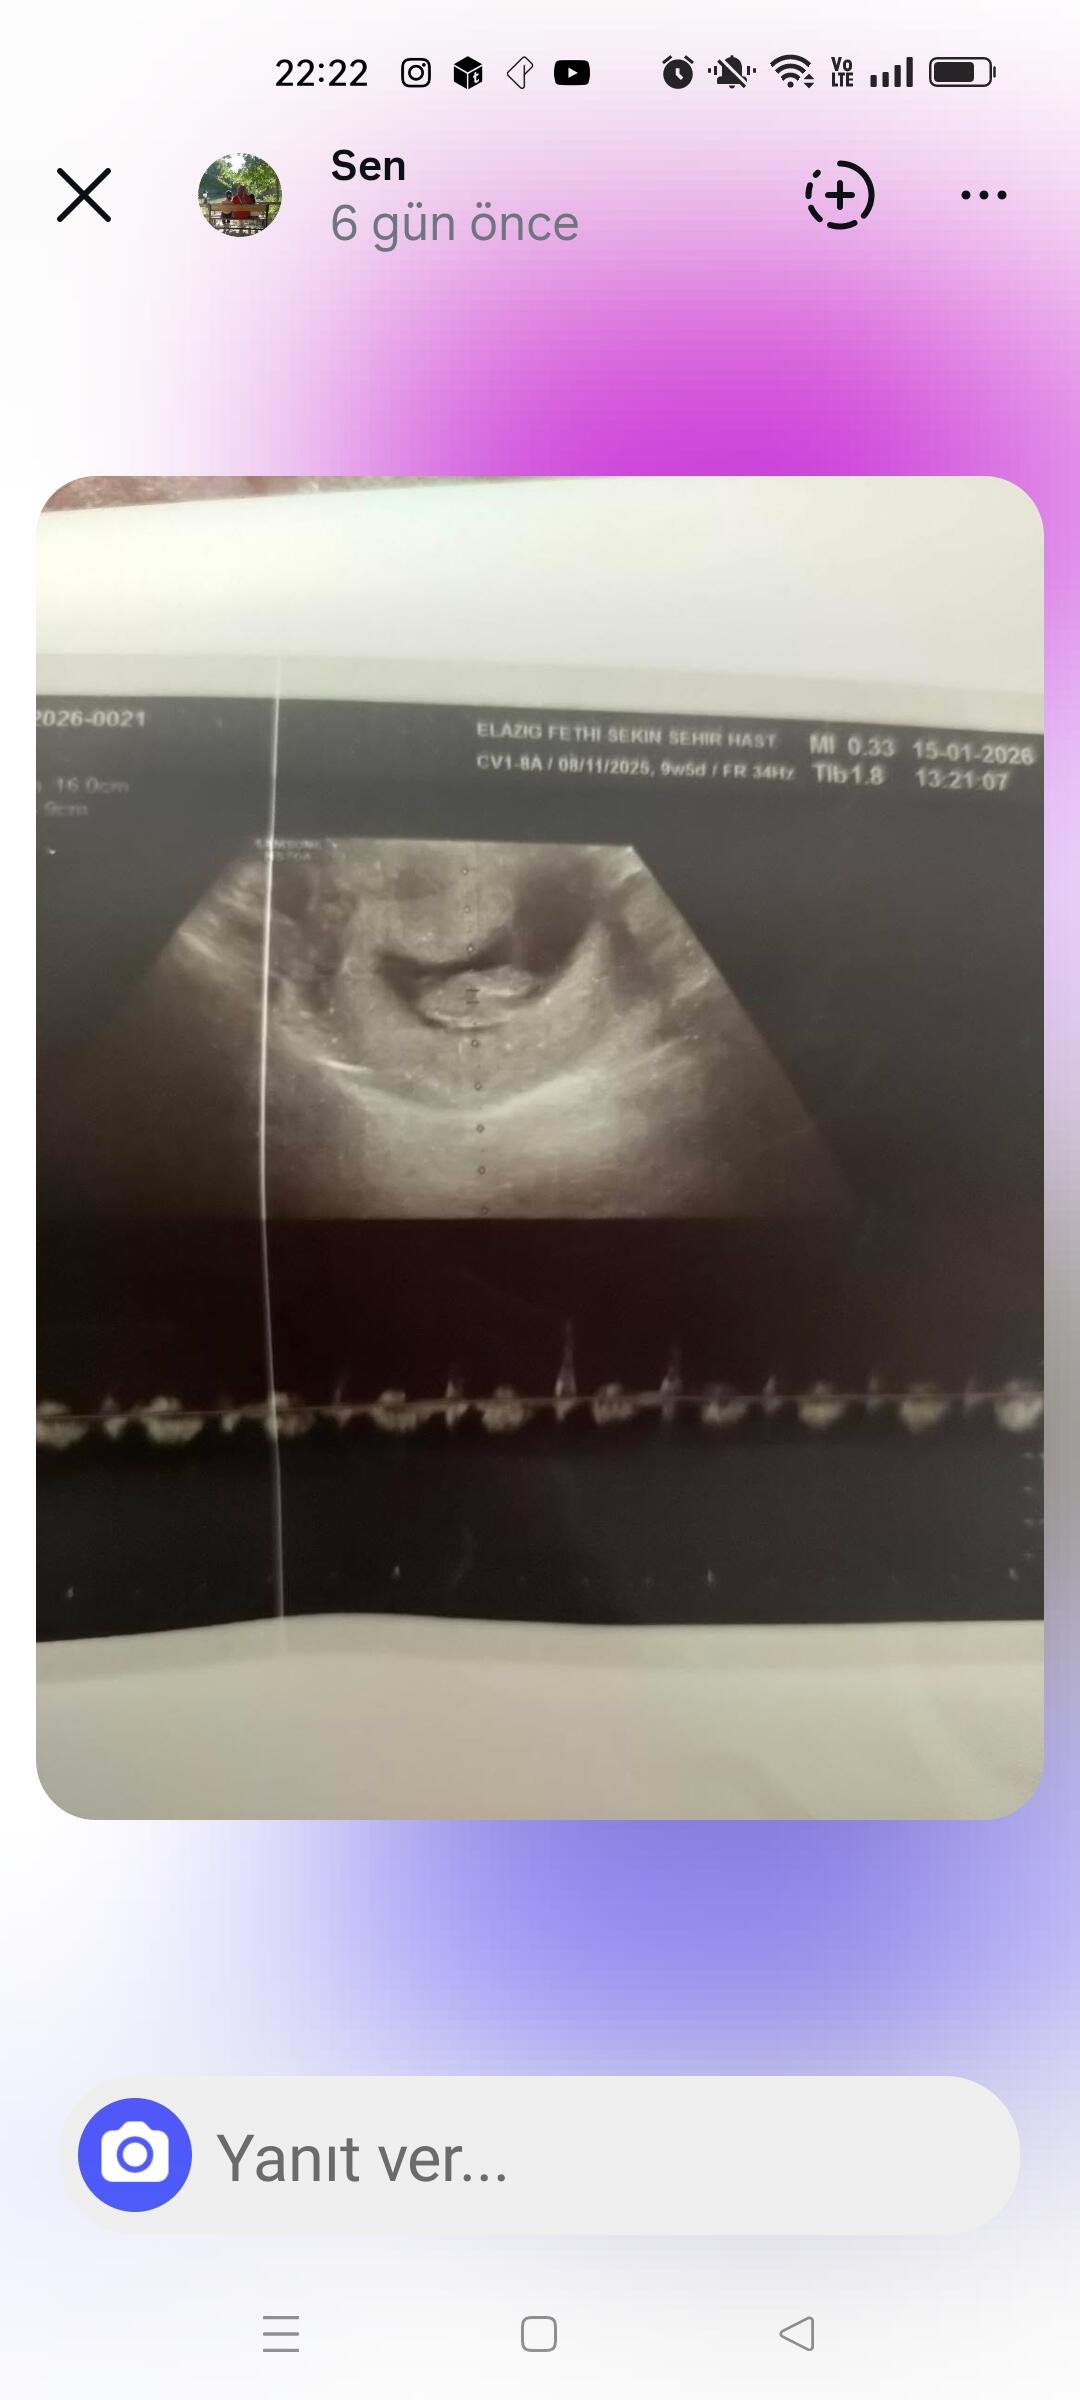

At cnm kaç haftalık oldu

Attımm bakar mısınızzz

Kız bence ya

Erkek gibi duruyo canim Allah bilir yine de boylu boyuna da yatiyo maaşallah Rabbim sağlıklı sıhhatli kucagina almak nasip etsin insallah canım

Kız gibi dedi Nuba göre

Erkek bebiş kuzum

Erkek gibi geldi bana da hayırlısını versin rabbim insallah canim allah sag salim sağlıklı bir sekilde kucagina almak nasip etsin insallah